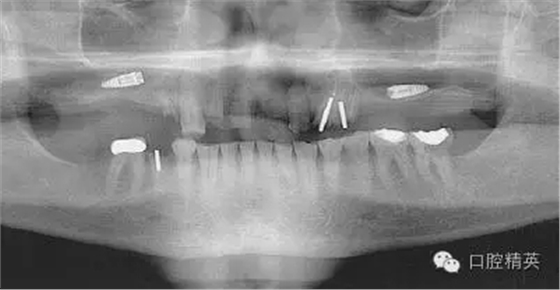

圖1a:術(shù)后根尖片顯示種植體傳入左側(cè)上頜竇

我們通過(guò)文獻(xiàn)和網(wǎng)站檢索獲得了一些關(guān)于種植體失敗的研究和綜述文章。一個(gè)和僅使用兩維放射診斷(根尖片或曲斷片)有關(guān)的常見(jiàn)失敗是上頜竇穿孔。(圖1a-c)通常牙醫(yī)由于錯(cuò)誤的估計(jì)了上頜竇底骨量高度而造成幾個(gè)毫米的上頜竇底穿孔。一些病例可能沒(méi)有癥狀,象圖中所示的這個(gè)病例,患者需要嚴(yán)格的監(jiān)控、復(fù)查。有些病例則出現(xiàn)并發(fā)癥,種植體不得不取出。

有些醫(yī)生主張?zhí)匾庵圃焐项M竇穿孔,以獲得“雙層骨皮質(zhì)固位”,增加種植體初期穩(wěn)定性。但是,2000年發(fā)表的一篇15年的回顧性研究顯示:雙層骨皮質(zhì)固位的種植體的失敗率比單層皮質(zhì)骨固位高4倍。失敗原因80%以上為種植體折斷,而其發(fā)生于雙側(cè)皮質(zhì)骨固位的種植體的幾率比單層皮質(zhì)骨固位高3倍。

另一個(gè)和醫(yī)生僅用兩維放射線檢查造成的特殊并發(fā)癥是種植體進(jìn)入上頜竇。(圖2a-c)可能成為上頜竇異物的有牙齒,牙根,印模材料,牙科器械,近年來(lái)又增加了一個(gè)—種植體。可想而知,從上頜竇中取出異物對(duì)患者來(lái)講是創(chuàng)傷很大的。

其他研究也報(bào)道過(guò),對(duì)于這種病例,唯一的選擇是用根管顯微鏡或Caldwell Luc技術(shù)從上頜竇中取出種植體。有些文章報(bào)道了如何處理進(jìn)入上頜竇的種植體,但很少?gòu)念A(yù)防的角度來(lái)談這個(gè)問(wèn)題,其實(shí)很簡(jiǎn)單,術(shù)前應(yīng)該應(yīng)用CBCT成像檢查。